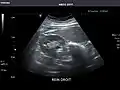

Renal ultrasonography

Ultrasound scan of a kidney (right side)

Ultrasonography of the kidneys is essential in the diagnosis and management of kidney-related diseases. The kidneys are easily examined, and most pathological changes in the kidneys are distinguishable with ultrasound.[7]